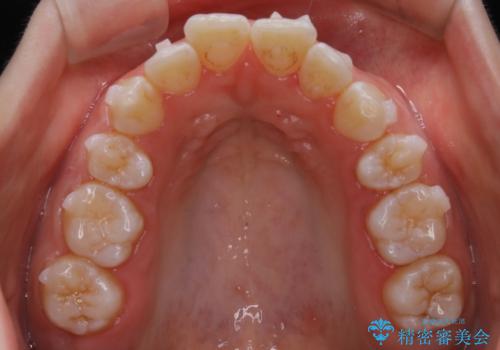

【非抜歯】上下の前歯が噛み合わないオープンバイトの治療

- 噛み合わせの不調を主訴にご来院されました。

骨格的な問題もあり、噛んだ時に奥歯しか当たらず前歯の被蓋があまりない状態でした。

臼歯の位置が高く噛んだ時に奥歯しか当たらなかったり、舌癖などが原因で前歯が前に倒れてしまうことで上下の前歯の被蓋がなくなってしまっている状態をオープンバイトといいます。

前者の場合は臼歯を圧下し沈めてあげることで改善させます。後者の場合は前方に傾斜している歯を元の角度に戻してあげることで改善しますが、舌癖がある場合はその癖自体を無くす治療をしない限りまた同じ状態へと後戻りしてしまいます。